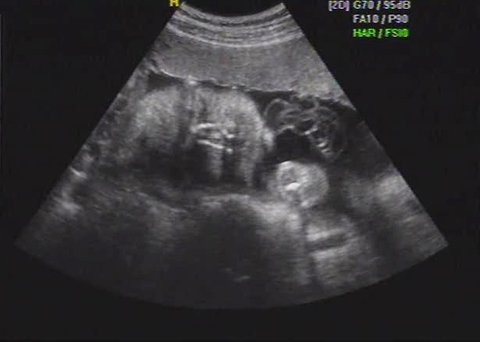

[ 임신 27주 마오 모습 ]